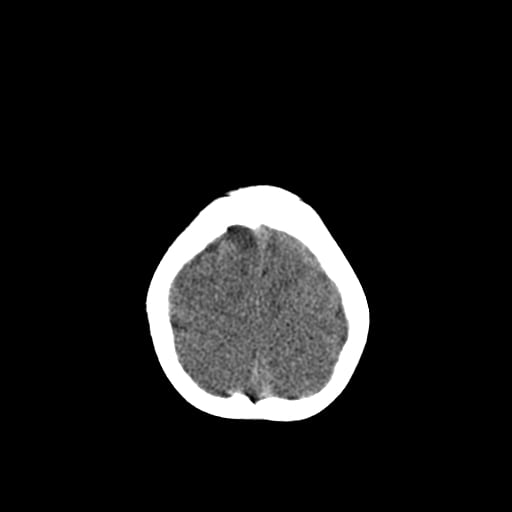

Age: 1

Sex: Male

Indication: Fall